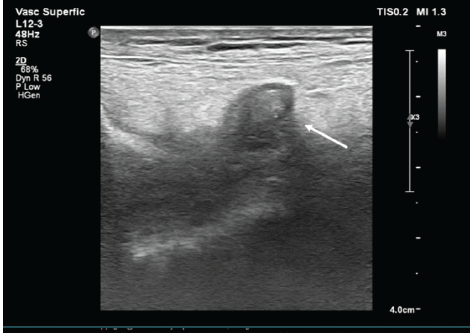

The patient was referred to the interventional radiology team and managed with ultrasound-guided compression. A high-frequency 7–12 MHz linear transducer was used, and sustained probe compression was applied directly over the pseudoaneurysm neck in approximately 30-min cycles under real-time Doppler guidance, with intermittent assessment of intralesional flow. After two sessions, complete disappearance of color flow within the sac was observed, confirming successful thrombosis of the pseudoaneurysm, which was subsequently replaced by an echogenic hematoma (Fig. 4).

Figure 4: Post–ultrasound-guided compression grayscale ultrasonography of the right knee demonstrating an echogenic thrombus within the pseudoaneurysm sac, indicating successful thrombosis and obliteration of the lesion (white arrow).